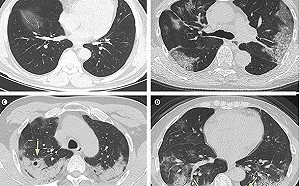

這照片最近在中國到處可見! 大「白肺」驚人 醫師 : 罹患者性命堪憂